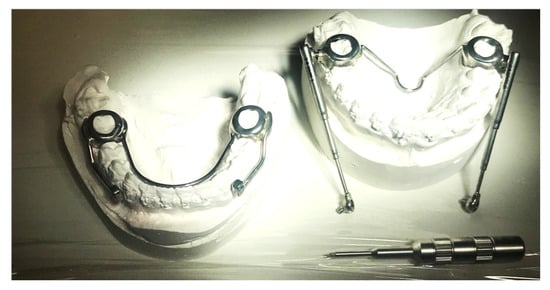

The Herbst device can be modified by not providing the bands on the premolars. It has an arm welded onto the band of the lower molar, which extends horizontally up to the lower first premolar. The arm is spaced from the mucosa by approximately 1 mm to reduce the bulk in the oral fornix and is positioned approximately at the height of the gingival margin of the lower bicuspid. The joint of the telescopic tube is inserted at this point of the arm, which, in this version of the device, allows greater freedom in lateral movements thanks to its characteristics. The telescopic tube at the top fits onto another joint welded onto the band of the upper sixth. This allows the presence of the appliance on the upper arch to be limited to the first molars, while the rest of the upper arch is not obstructed. The design of the band provides almost total occlusal coverage to increase band retention and control over the dental effects of the applied forces (Figure 5). A space between the welded arm and the teeth must be guaranteed in order to facilitate the oral hygiene routine for the patient (Figure 6).

Figure 5.

Simplified design of the Herbst appliance.